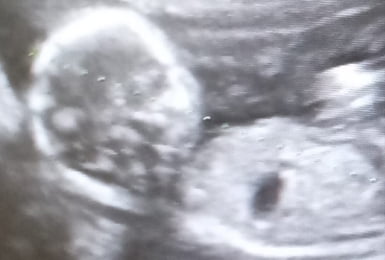

Maintenant Leticia et en repos absolu avec son bébé dans son ventre, la petite Maria Magdalena qui attend de venir au monde en juin prochain. Je vous envoie une photo de la dernière écographie de ce petit-grand miracle de la vie !